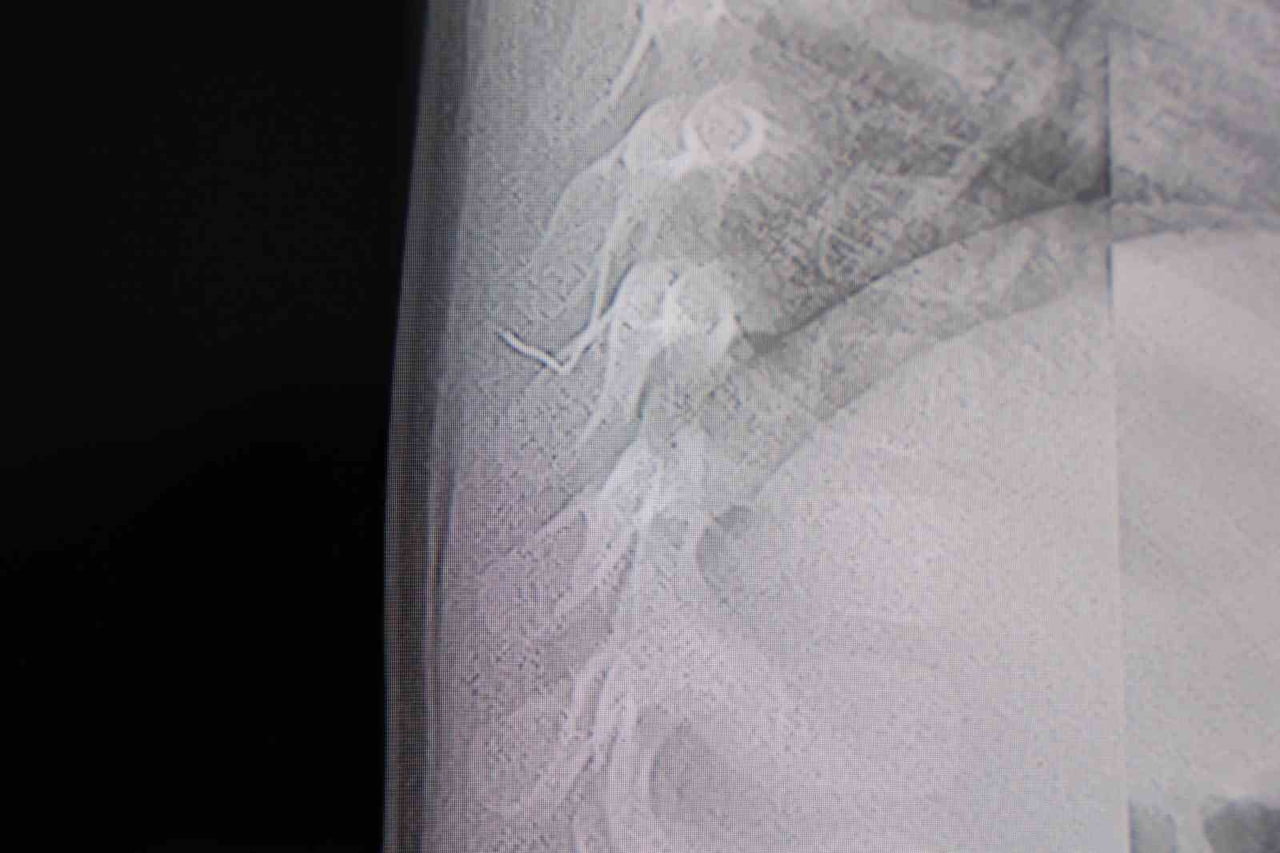

HG Hospital Beyin ve Sinir Cerrahisi Uzmanı Prof. Dr. İdris Altun tarafından gerçekleştirilen tetkiklerde, yabancı cismin cilt altında, omurilik kanalına oldukça yakın bir bölgede olduğu ve akciğer zarına doğru ilerlediği belirlendi. Müdahale, hastayı tamamen genel anesteziye almadan, lokal anestezi ve sedasyon eşliğinde yapıldı.

Operasyonda yabancı cisim tamamen çıkarıldı. Çıkarılan cismin ince zımba teline benzer metal bir tel olduğu ve yaklaşık 2 santimetre uzunluğunda bulunduğu tespit edildi. Bebeğin durumu ameliyat sonrası stabil bulundu ve aynı gün taburcu edildi.